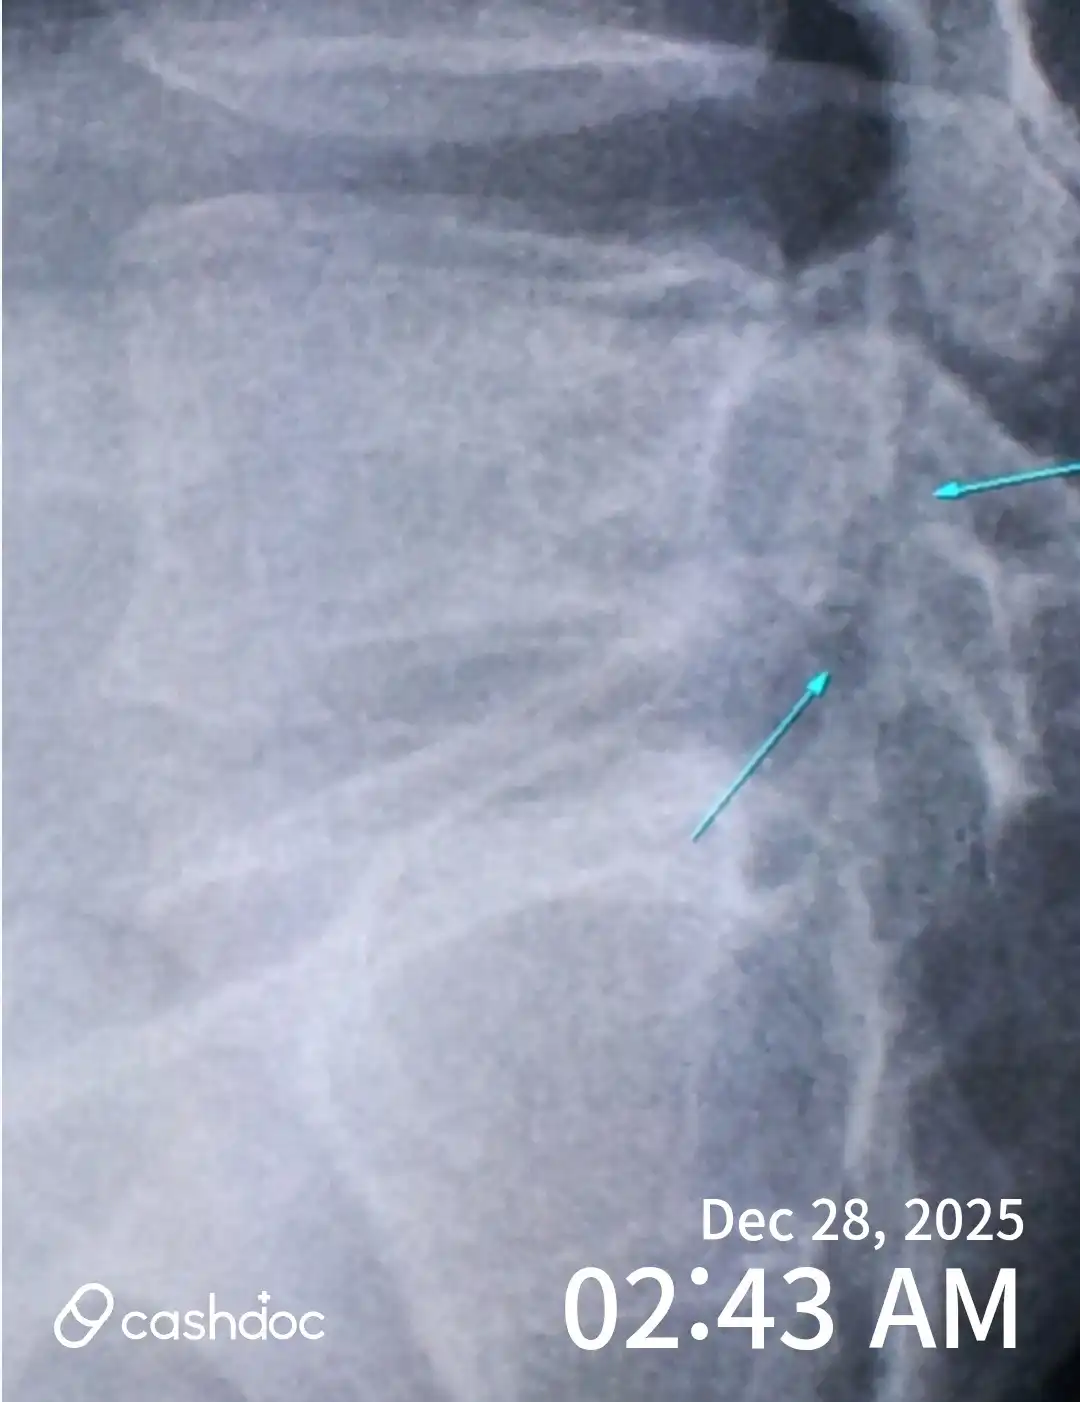

두근*25.12.281번째 방문 아이가 학교 체육시간에 피구를 하다가 공을 잘못 받는 바람에 손가락이 심하게 붓고 통증을 호소해 급하게 정형외과를 방문했습니다. 접수 후 비교적 빠르게 진료를 받을 수 있었고, 엑스레이 촬영을 통해 손가락 골절이라는 정확한 진단을 받을 수 있었습니다. 담당 선생님께서 아이 눈높이에 맞춰 현재 상태와 골절 부위, 회복 과정에 대해 차분하게 설명해 주셔서 보호자로서도 안심이 되었습니다. 단순히 “골절입니다”로 끝나는 것이 아니라 왜 고정이 필요한지, 언제까지 조심해야 하는지, 학교생활 중 주의사항까지 자세히 안내해 주셨습니다. 깁스 고